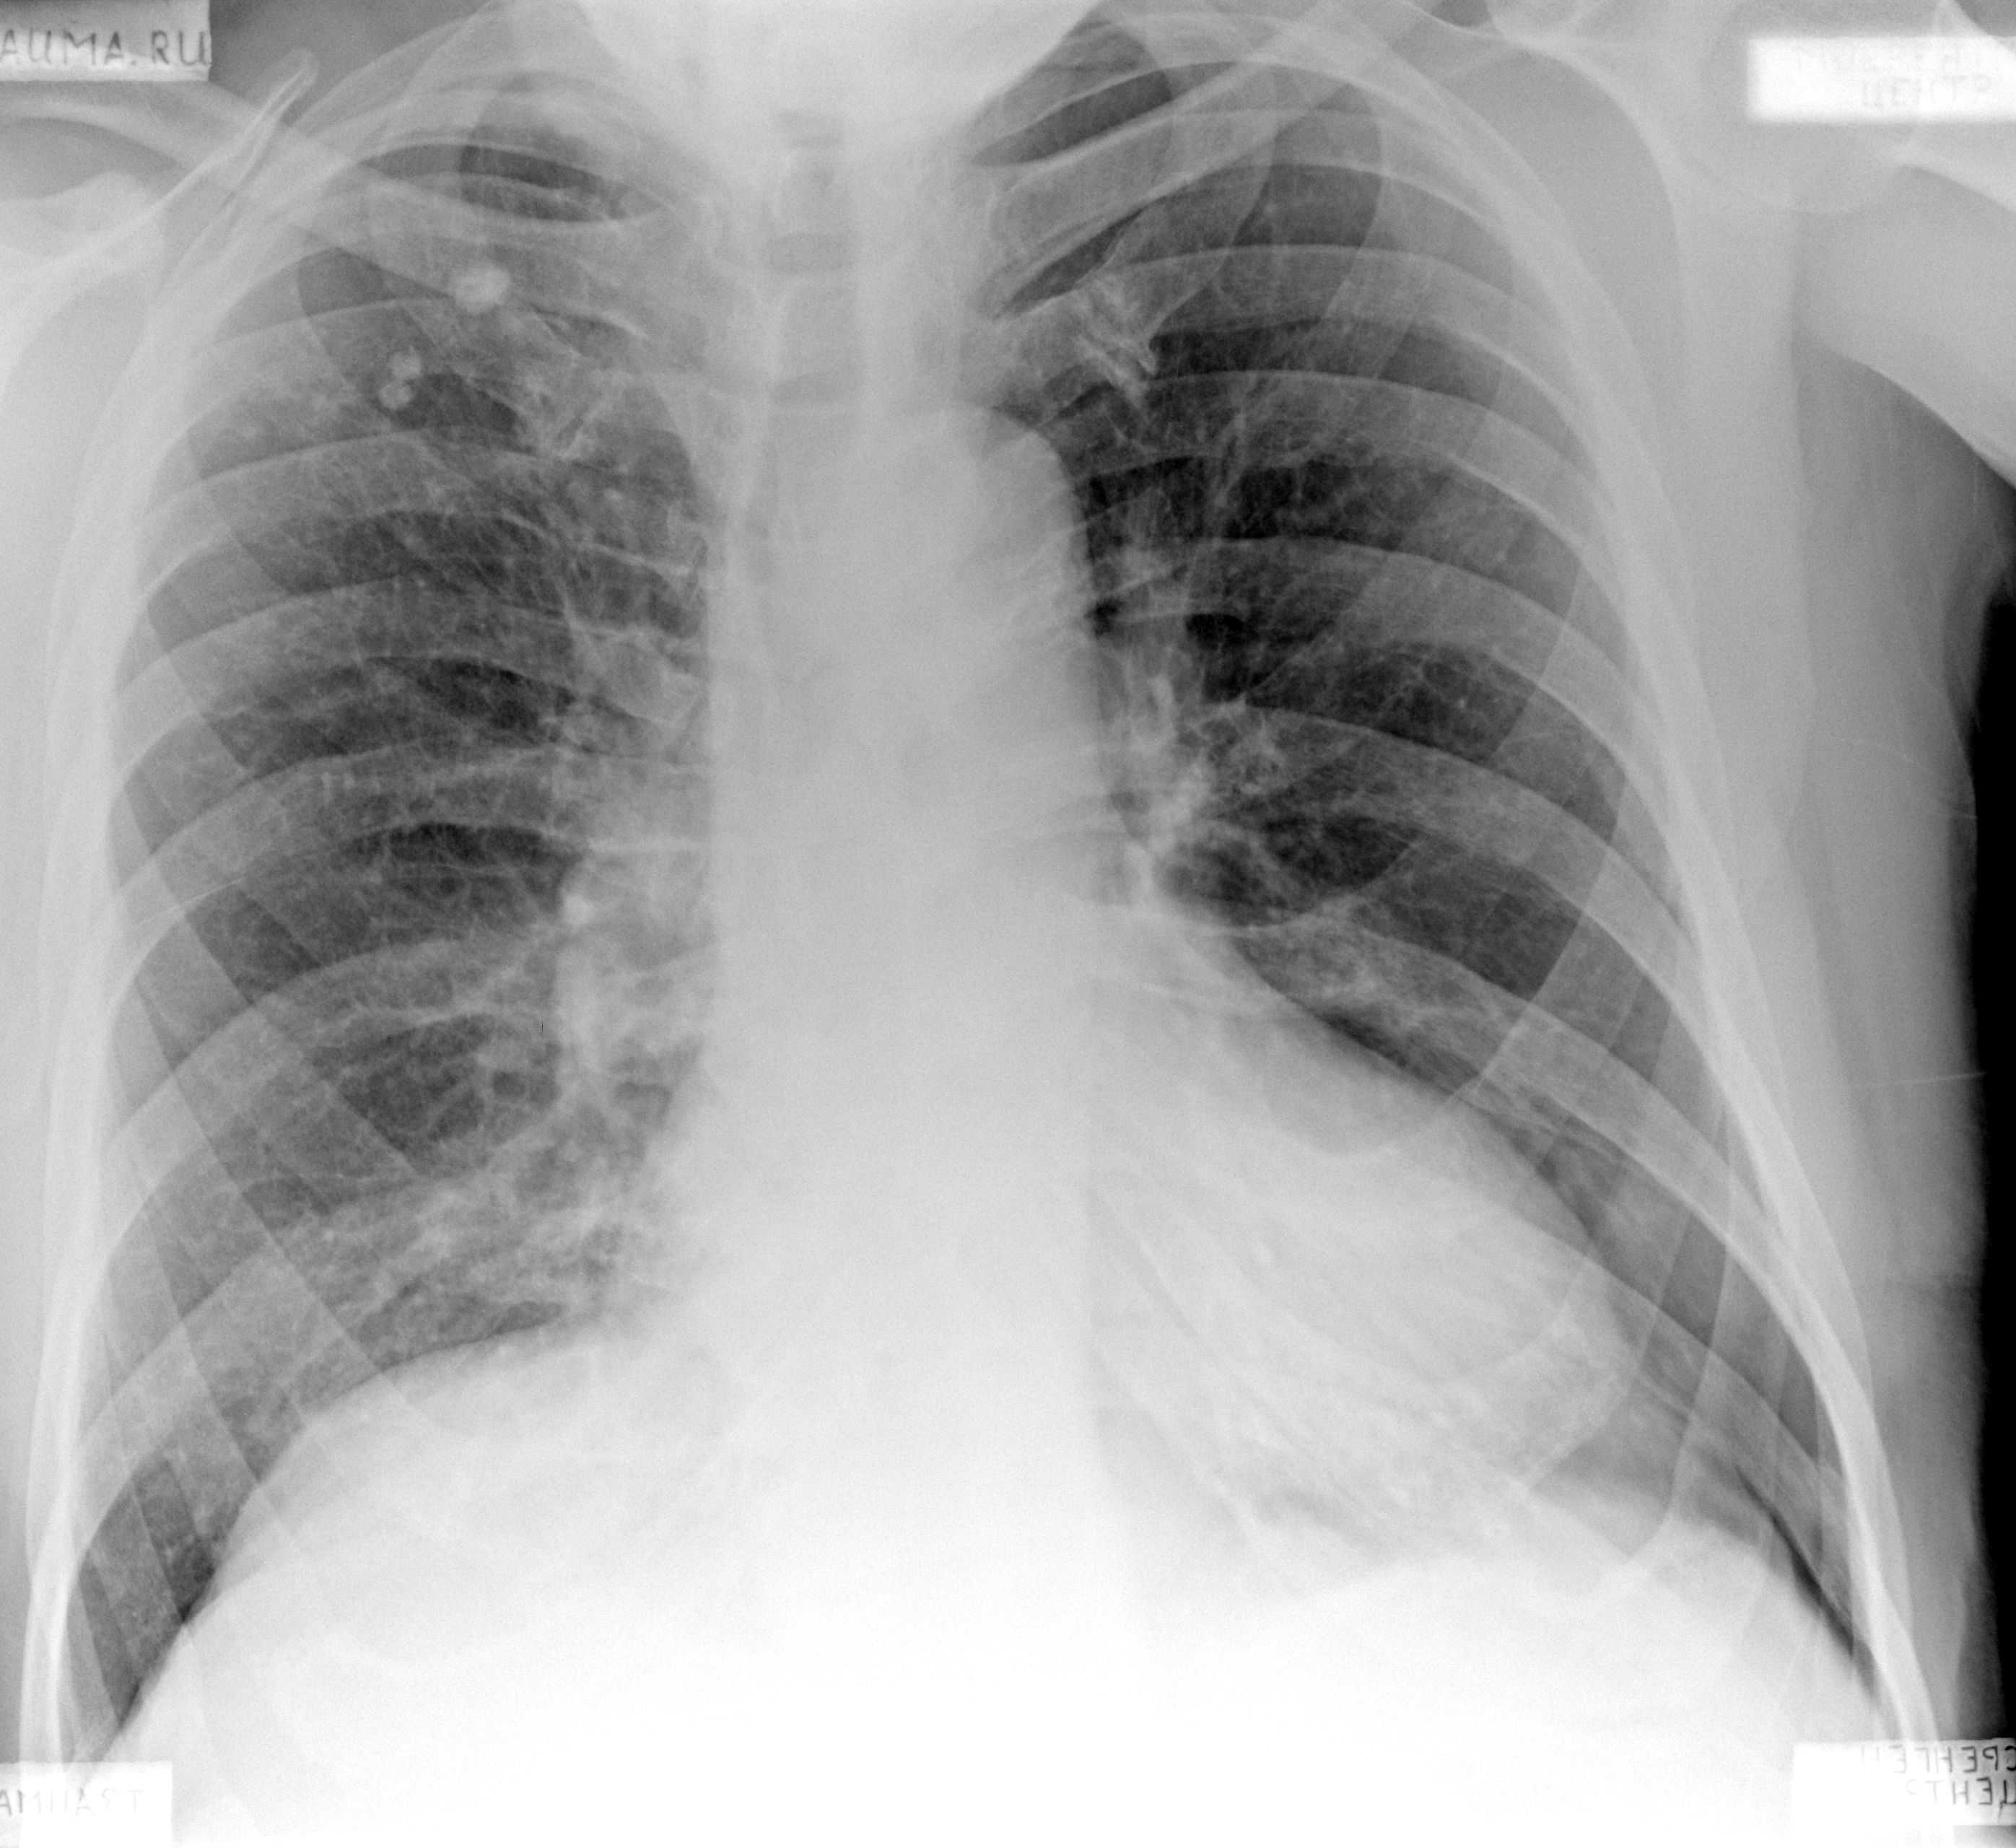

Рентгеновские снимки при пневмоцистной пневмонии